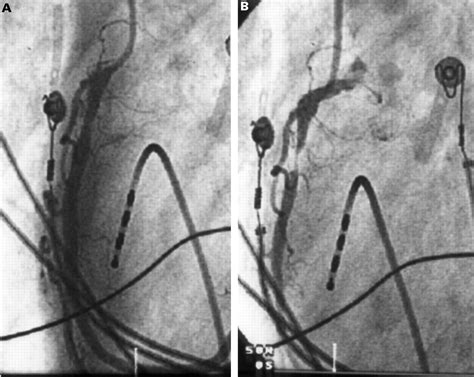

• Coronary angiography: This invasive procedure involves inserting a catheter into the arteries to visualize blood flow and identify any blockages or spasms.